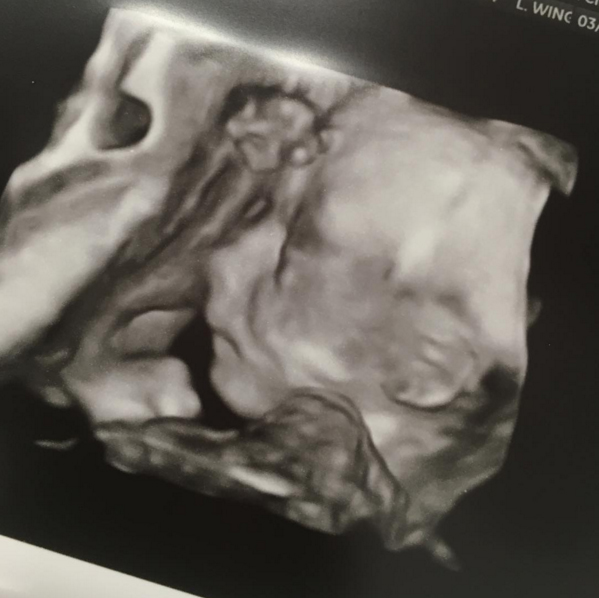

First of all, I’m glad that after the ultrasound we found out that our little guy is growing and doing great. It definitely set this mama’s mind at ease going into my 22nd week of this pregnancy. A healthy baby is all I’ve ever prayed for and will continue to do so until he is placed in my arms.

BabyB2[he looks exactly like his big brother]